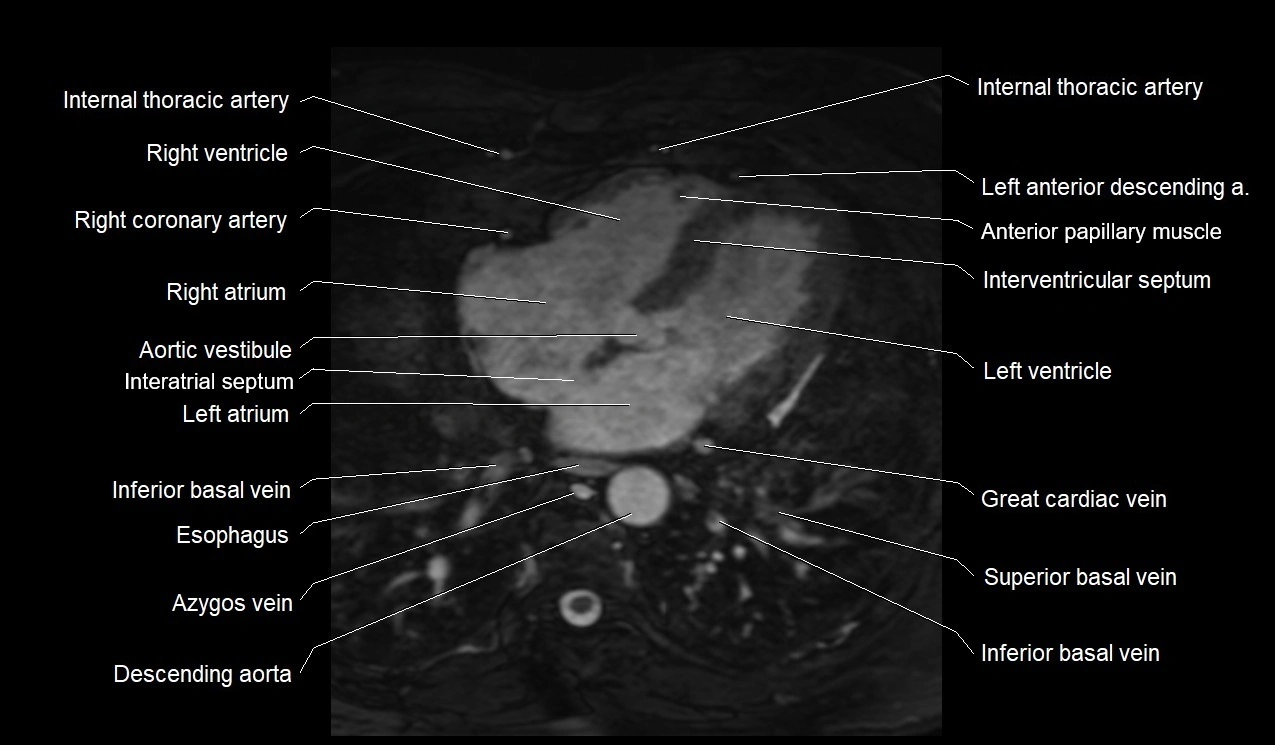

MRI image